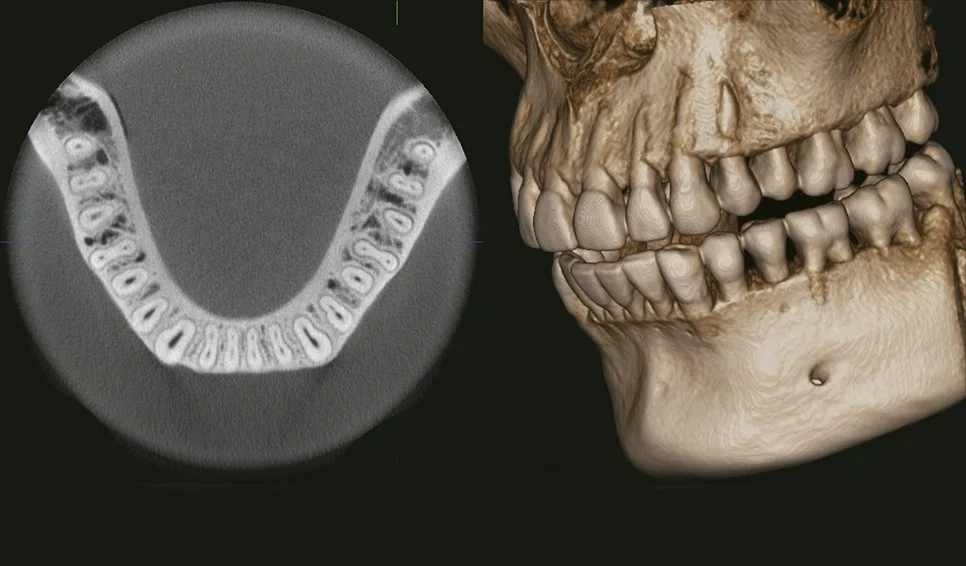

Con nuestros equipos podemos obtener imágenes panorámicas, de perfil y en 3 dimensiones con gran nitidez, gracias a su sistema innovador que sigue perfectamente la curva natural de tus dientes, consiguiendo ver toda tu boca de la forma más clara posible, enfocándonos solo en lo que realmente importa: diagnósticos mucho más precisos con la menor radiación necesaria.